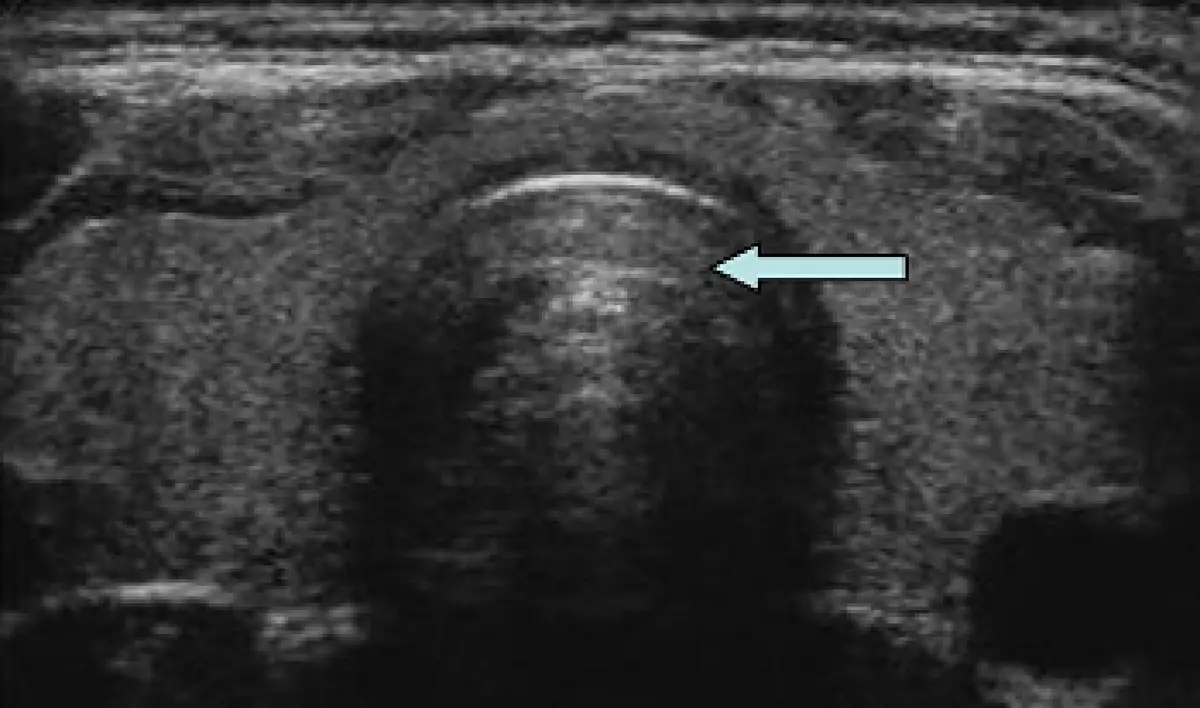

附圖是人體甲狀腺橫向超音波影像,箭號所指處應屬何器官?

本影像為頸部甲狀腺橫切面超音波影像。

- 中央主要構造:影像正中央可見一個圓形高回音弧狀前壁的構造,其後方緊接一大片後方聲影(posterior acoustic shadowing),呈現明顯黑色無回音區,向下延伸至影像底部

- 藍色箭號所指:箭號由右向左,指向中央圓形構造偏左側處,即有後方聲影的主體構造

此後方聲影的影像特徵是辨識的關鍵:氣管內充滿空氣,由於空氣與組織之間的聲阻抗(acoustic impedance)差異極大,超音波波束在氣管前壁的空氣-組織界面幾乎完全反射,造成其後方完全無法成像,形成典型的大片後方聲影(air reverberation artifact)。

此構造位於頸部正中線,兩側甲狀腺葉之間,具有典型的氣管超音波表現:前壁可見、後壁因聲影而不可見,符合氣管的特徵。